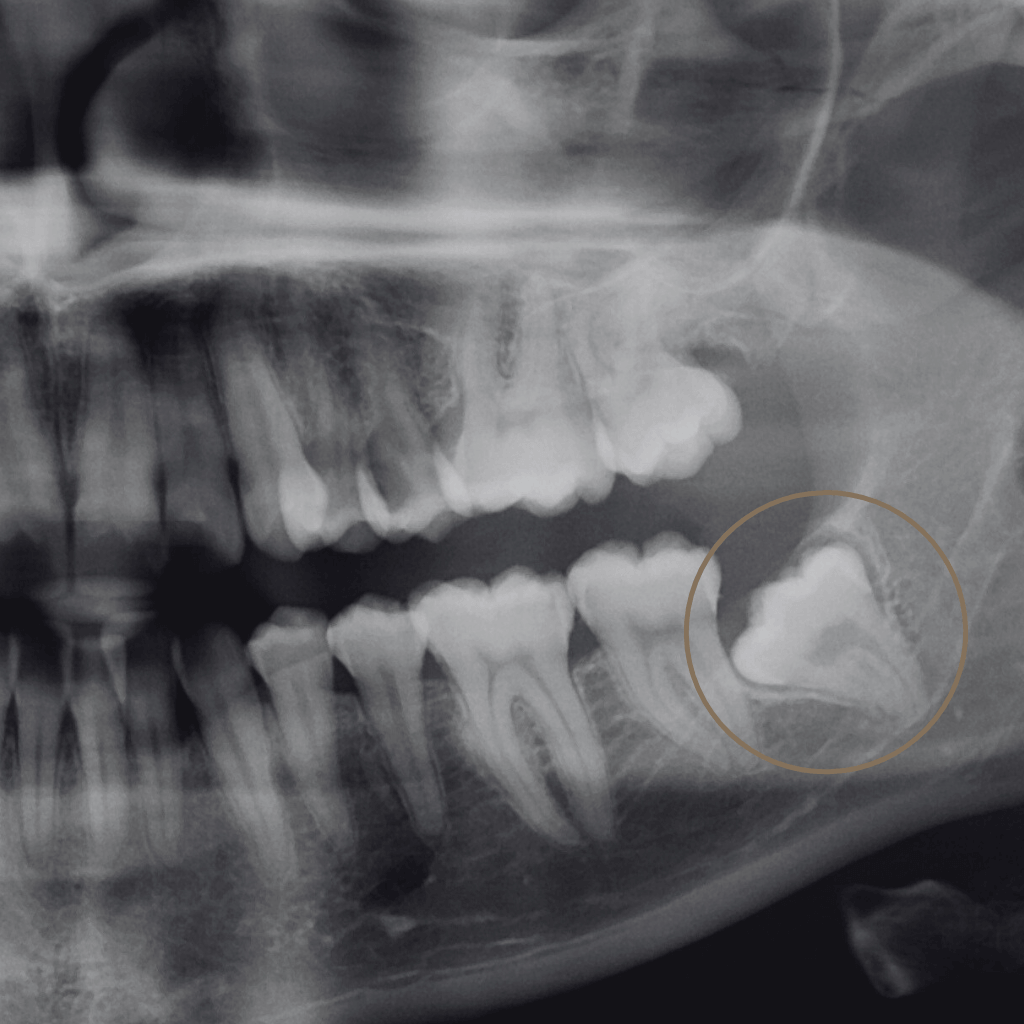

Екстракцията е хирургична процедура, при която зъбът се отстранява, когато неговото запазване не е възможно или би компрометирало цялостното орално здраве. В Aesthetico екстракциите се извършват след внимателна оценка и с ясна цел – лечение, облекчаване на болката и създаване на стабилна основа за последващи стъпки.